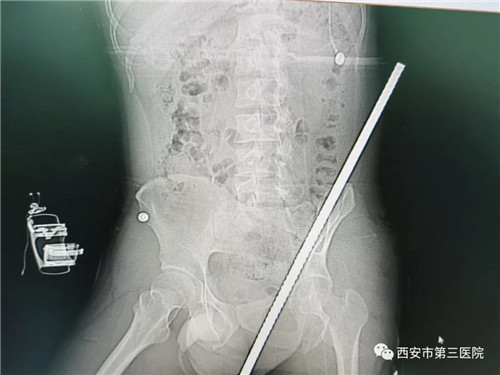

9月8日,一男子在某工地不慎从高处坠落,被一根直径约2厘米粗长约1米的钢筋从会阴部刺入,从左侧腹部穿出。

在医教部的统筹指挥下,手术由麻醉科蒯建科主任团队麻醉,手术室千冬维、程彦英护理团队配合,普外科遆振宇主任团队、骨科吕昌伟主任团队、泌尿外科任宝明团队主刀。麻醉科杨倩医师迅速建立有创动脉血压监测,中心静脉快通道,最短的时间内建立了人工气道,大家将患者小心翼翼转移至手术台,避免钢筋在体内引发二次损伤。随着手术的进行,在多个学科精诚协作下,专家们紧皱的眉头也逐渐放松,感慨道:“不幸中的万幸是,钢筋虽然贯穿患者腰腹部,但从大血管和肠管、重要脏器之间穿插而过!”尽管情况不算最坏,但也是九死一生。